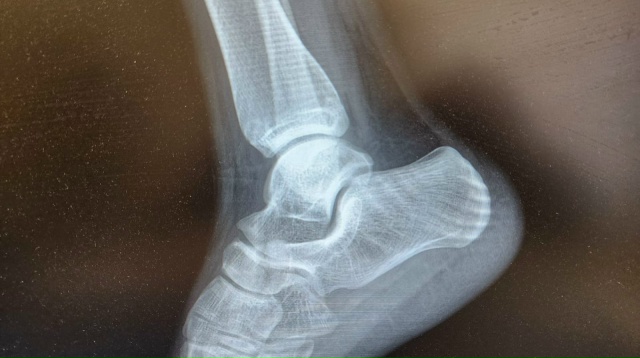

За прошедшую неделю со 2 по 8 марта врачи амбулаторно-травматологического центра Больницы скорой медицинской помощи Рязани оказали помощь 578 пациентам. В пресс-службе БСМП , что за указанный период 166 человек обратились с переломами, 208 с ушибами, 110 с растяжениями, ещё 24 с ранами.

Рязанцам напоминают, что амбулаторно-травматологический центр оказывает травматологическую, специализированную и неотложную помощи населению с травмами опорно-двигательного аппарата в режиме 7/24 без праздников и выходных.